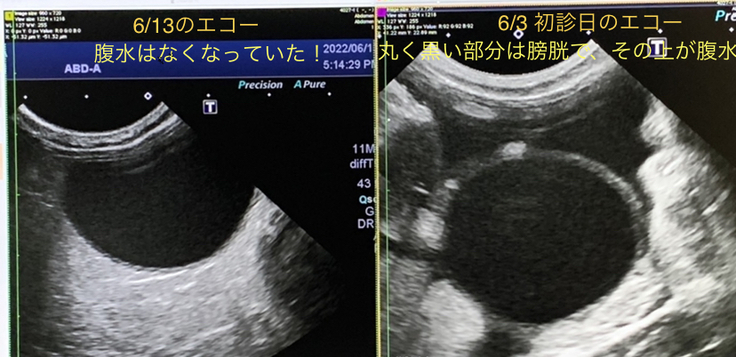

③6/13 定期受診で採血と腹部のエコー検査をしました。

※病院からの掲載許可は得ています。

10日間で劇的に腹水改善!まるで魔法?と思いました。

入院・点滴・治療していただいた先生方に改めて感謝!

そして、頑張って治療を受けている小さなララに生きてくれていることの感謝!